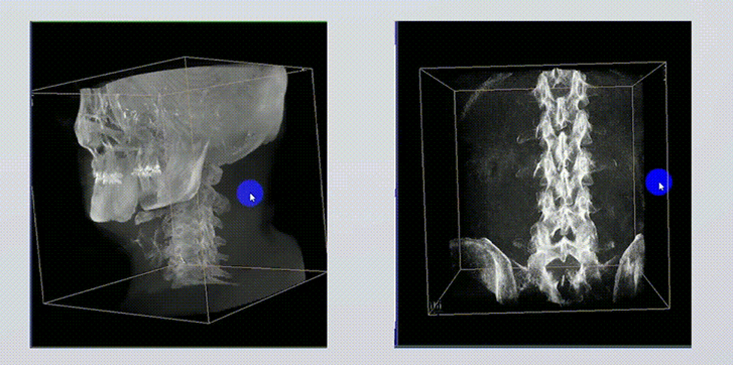

1、術(shù)中實(shí)時(shí)三維成像

術(shù)中三維成像和橫斷面圖像提供多角度的手術(shù)診斷信息,輔助醫(yī)生進(jìn)行術(shù)中評(píng)估判斷,諸如骨折復(fù)位情況和內(nèi)植入螺釘?shù)某叽绾臀恢茫o助手術(shù)更好地完成。

2、三維成像視野大

提供更大的術(shù)中三維成像視野,采集更多圖像信息,可一次拍全全段頸椎、全段腰椎、七節(jié)胸椎、雙側(cè)骶髂關(guān)節(jié)、股骨頭及單側(cè)盆骨。